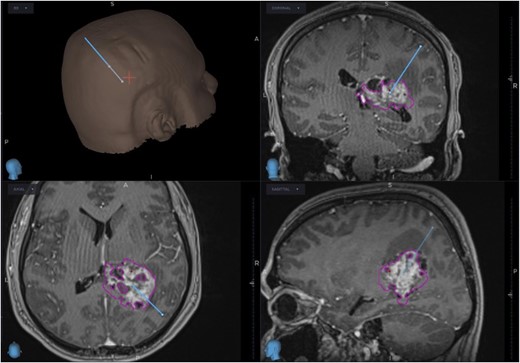

The patient was started on oral dexamethasone, resulting in the improvement of his headaches. The differential diagnosis based on imaging findings included an atypical meningioma, central neurocytoma, choroid plexus papilloma or carcinoma, ependymoma or an oligodendroglioma. He underwent a right parietal craniotomy with gross total resection of the lesion. Intraoperatively, use of the Vycor™ ViewSite Brain Access System (VBAS) was utilized, which allowed for optimized surgical site access, and reduced the risk of brain retractor injury to surrounding structures, namely the precentral gyrus. This was combined with intraoperative ultrasound (Fig. 3), which provided real time imaging and guided the extent of the resection. In addition, neuromonitoring and neuronavigation (Fig. 2) were incorporated to further reduce the risk of damage to surrounding structures. As part of the neuromonitoring, motor evoked potentials (MEPs) were performed to identify the precentral gyrus prior to insertion of the VBAS (Fig. 4), ensuring that any resection occurred posterior to the motor strip. During surgery, it was noted that the lesion was haemorrhagic and easily friable, with evidence of a previous recent haemorrhage.

Intraoperative image depicting the use of MEPs to identify the precentral gyrus, prior to insertion of the VBAS. In this image, the anterior aspect of the head is to the right, whereas the posterior aspect is to the left.